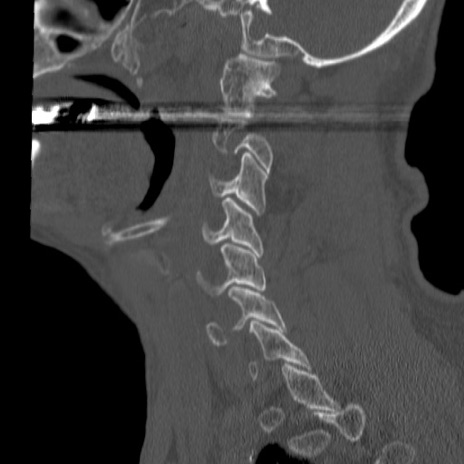

症例46 頚椎CT(矢状断像)

【症例】80歳代男性

【主訴】両側頚部〜上肢のしびれ

【現病歴】昨日、自宅内で転倒、その後より上記症状あり。意識障害なし。

【身体所見】両側上肢のallodynia(熱痛覚過敏)あり。MMTおよびDTRは正確な所見取れず。両上肢の挙上はなんとか可能。

異常所見と診断は?